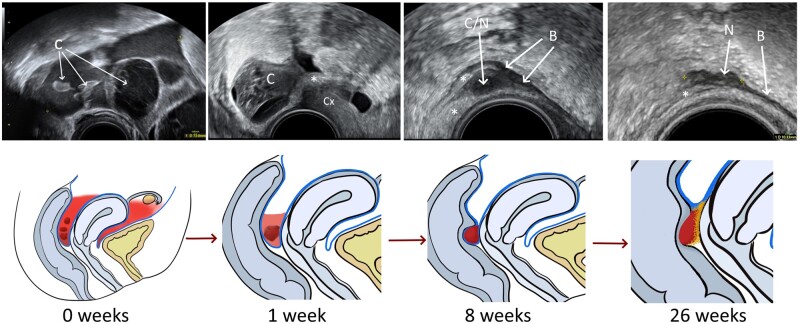

Main results and the role of chance: After completion of follow-up, 7/15 (47%; 95% CI 21.3-71.4%) women presenting with acute haemoperitoneum (study group) developed sonographic evidence of deep endometriosis, compared to 0/36 (0%; 97.5% CI 0.0-9.7%) women in the control group. A ruptured functional haemorrhagic cyst was the most common cause of haemoperitoneum, occurring in 13/15 cases (87%). The time from the initial event to sonographic evidence of endometriosis varied from 2 to 6 months. The EuroQol visual analogue scores were not significantly different at baseline between the groups that developed and did not develop endometriosis [28 (interquartile range (IQR) 15-40, n = 6) vs 56 (IQR 35-75, n = 44), P =0.09], while the EuroQol-5D values were lower in the endometriosis group [-0.01 (IQR -0.07 to 0.19, n = 6) vs 0.62 (IQR 0.24-0.73, n = 44), P =0.002]. At 6 months, the EuroQol-5D scores were improved in both groups, but remained significantly lower in the endometriosis group compared to the no endometriosis group [0.69 (IQR 0.66-0.80, n = 6) vs 0.85 (IQR 0.76-1.00, n = 44), P =0.03]. There was no clinically relevant difference in the pelvic pain scores at either time point.

Limitations reasons for caution: It remains uncertain whether minimal, superficial endometriosis existed at commencement of the study and had a role in the development of deep endometriosis. Although the ultrasound findings were in keeping with deep endometriosis, this was not confirmed histologically. The pelvic pain and HR-QOL findings could have been influenced by the baseline scores being taken when the patient was admitted with acute pain. Also, the sample size was too small to draw reliable conclusions regarding the impact of newly developed endometriosis on QoL.